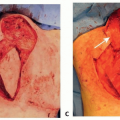

These glands are located in the subcutaneous tissue of the axilla and not in the dermis (FIG 1)—a fact that is of particular significance when considering the rationale for and effectiveness of axillary shaving in the treatment of hyperhidrosis.